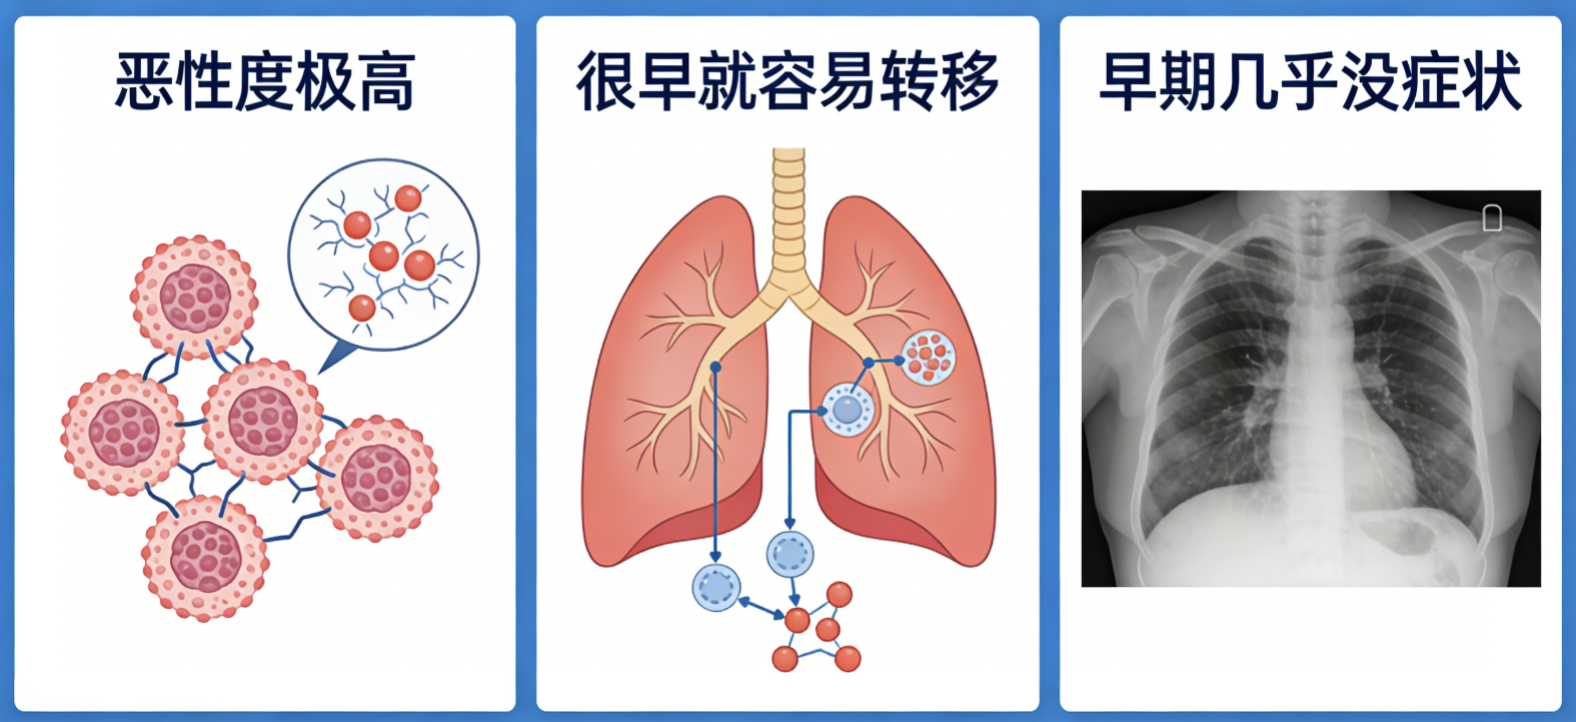

一、小细胞肺癌进展快的3个原因

1. 癌细胞恶性度极高

小细胞肺癌的分裂速度非常快,普通的肿瘤细胞可能几十天甚至上百天才翻倍,而小细胞肺癌往往只需要几天时间。天生就是“疯长型”肿瘤,比很多癌症都更凶猛,增殖能力极强。

2. 很早就容易转移

小细胞肺癌的第二个可怕之处,在于它极早期就具备转移能力。它非常擅长侵入人体的血管和淋巴管,就像一颗蒲公英种子,风一吹,四处飘散。临床上,很多患者刚确诊时,往往已经出现了肺门、纵隔淋巴结转移,甚至更严重的——脑转移和骨转移。

3. 早期几乎没症状

小细胞肺癌通常长在肺部的中心位置,早期不刺激胸膜,不堵塞大气道,患者根本感觉不到咳嗽、胸痛或胸闷。很多人都是在体检或者因为其他疾病拍片子时,才意外发现。

等到出现明显症状——比如胸闷气短、咳血、声音嘶哑、不明原因的体重急剧下降时,肿瘤往往已经大面积扩散,错过了最佳干预时机。